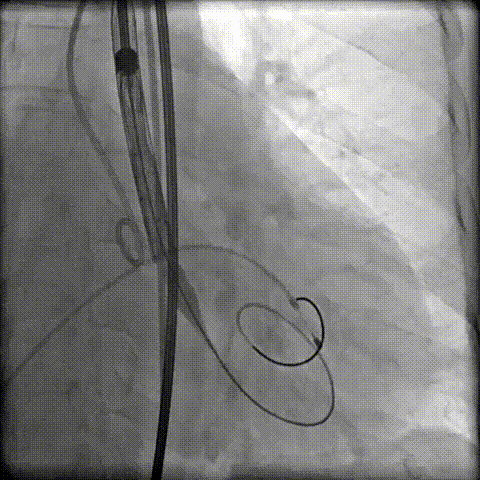

第二次定位释放

顺利脱钩撤鞘,瓣膜位置及形态理想,无明显瓣周漏